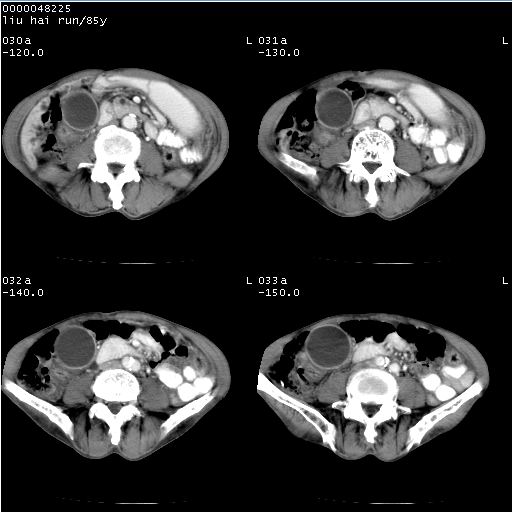

胆系低位梗阻。胰头占位

双肾多发囊肿

1.胆系低位梗阻,原因待查。建议进一步检查。2.双肾多发囊肿。

1)胆系低位梗阻(肝内外胆管扩张、胰管扩张、胆囊增大);考虑为:胰头癌可能性大,不排除胆总管下端癌。2)双肾多发囊肿。